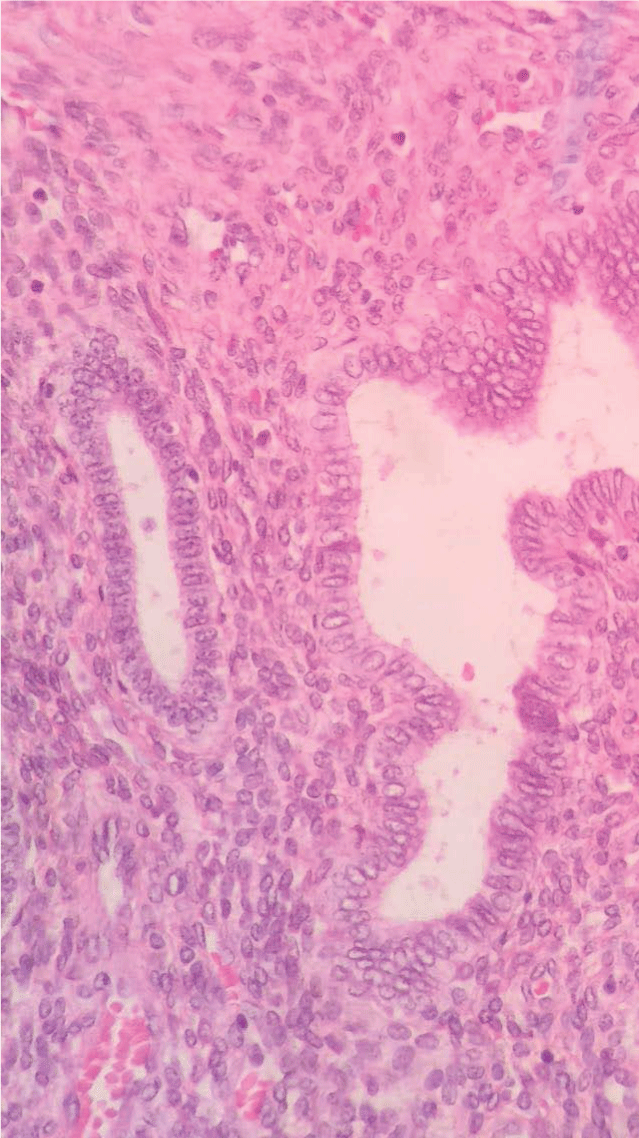

On the second postoperative day the patient was discharged without pain complaint and in good clinical condition. Histopathology analysis show presence of endometrial tissue in the myometrium, confirming adenomyosis (Figure 5 and Figure 6).

Figure 5: Histopathology analysis: presence of endometrial tissue in the myometrium.

Figure 6: Histopathology analysis: presence of endometrial tissue in the myometrium.